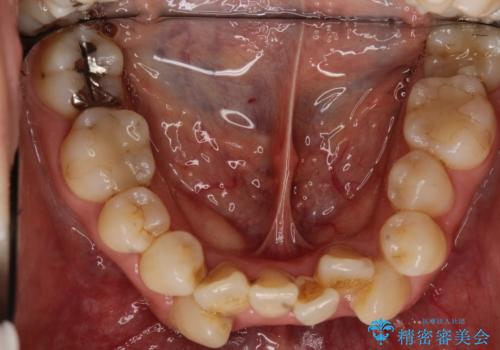

初診時の歯並びの状態としては、上下に強いガタガタがある状態であり、それが原因で口腔内の清掃状態も極めて悪い状況でした。

スペースの不足量が著しく、上下左右の抜歯を伴うワイヤー矯正にて治療を行いました。

抜歯によるスペースを利用し、強いがたつきの改善を行いました。

また、左上の奥歯に関して親知らずの1つ手前の歯の状態が悪かったため、その歯は抜歯をし親知らずを利用して噛み合わせを作りました。